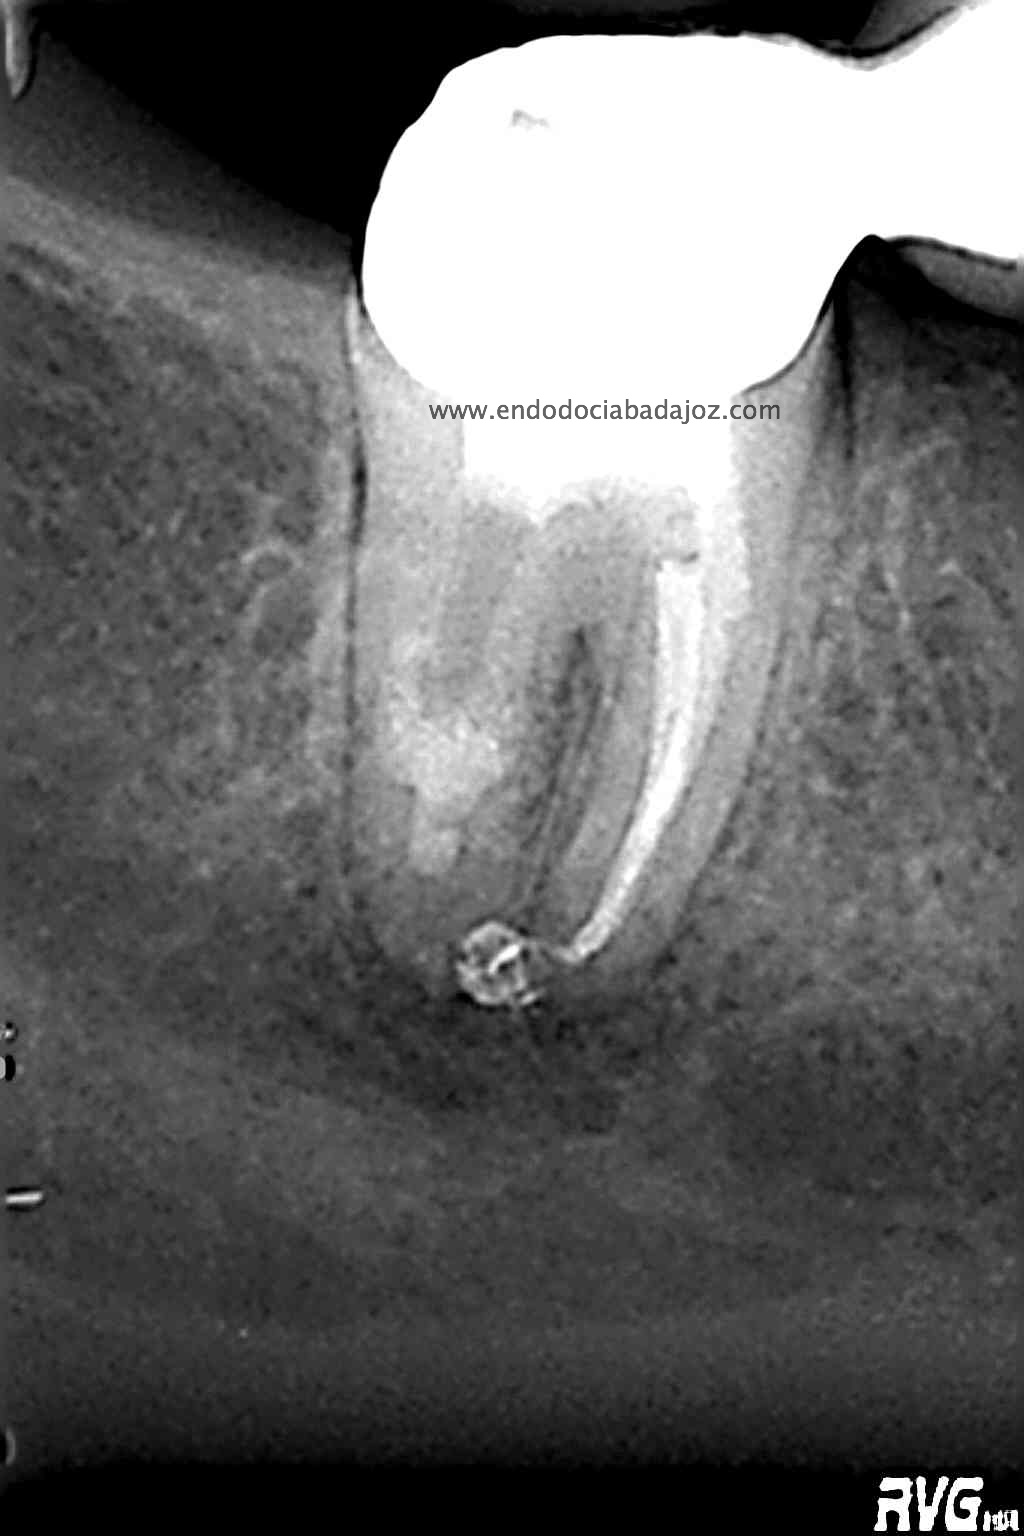

Acude a nuestra clínica una paciente que llamamos a revisión después de realizarle un retratamiento endodóntico de la pieza 4.7 hace unos meses. Si recordamos el día que llegó, no se nos presentaba muy bien el caso, y como otros muchos casos, intentamos retratarlo, pues pensamos que podríamos manejarlo.

Este caso lo resolveríamos en varias sesiones, después del manejo de los conductos mesiales, con una preparación biomecánica terminando en una conicidad del 6% y un diámetro apical de 30 en conductos mesiales.

Con ayuda del microscopio, pudimos confirmar que se trataba de una reabsorción interna en el tercio medio y una reabsorción radicular del conducto distal.

Bueno, pues el conducto distal se obturó en su tercio apical y medio con M.TA.

Hemos llamado a revisión a la paciente en varias ocasiones ( 6 meses y 9 meses)

(revision a los 6 meses) (revisión a los 9 meses)

Como podemos observar, la lesión periapical ha regenarado: